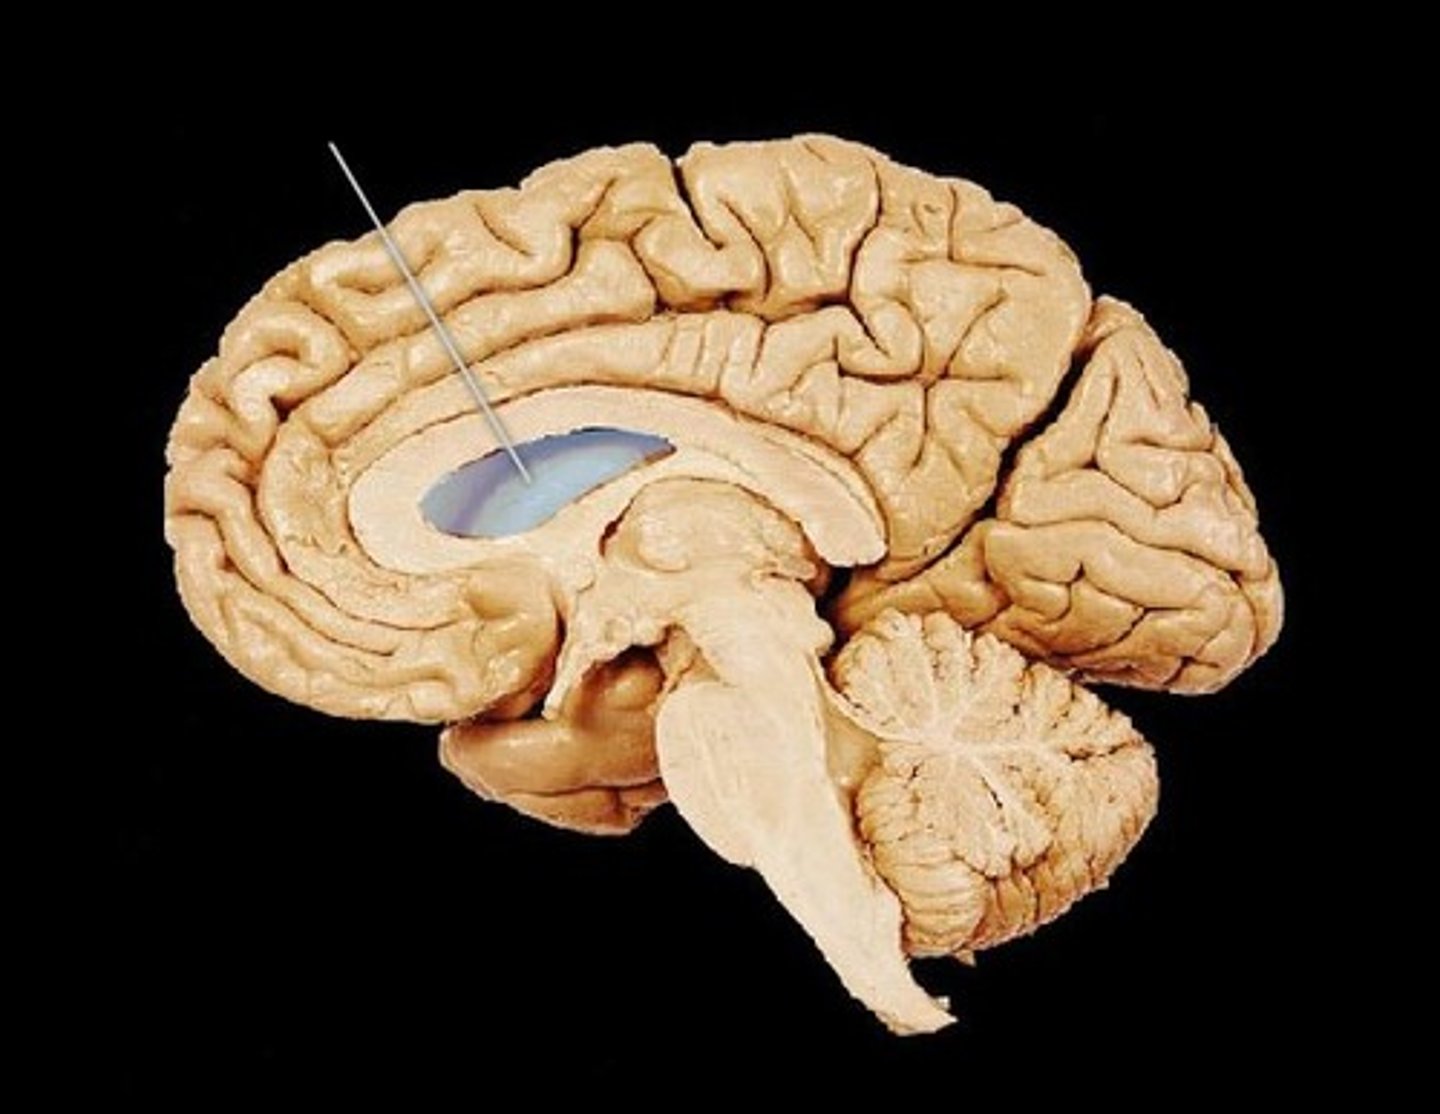

lateral ventricles

3rd ventricle